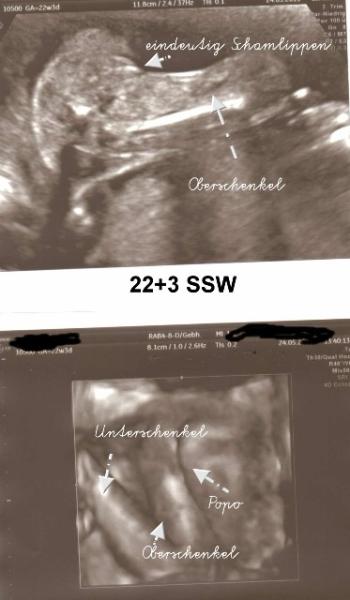

ein MÄDCHEN Kann es noch gar nicht fassen, nach drei Jungs kommt nun unser Mädchen. War heute beim 3D/4D US und es war eindeutig und dabei hieß es noch vor einer Woche das es wahrscheinlich ein Junge wird. Bin ja so überglücklich und könnte die ganze Welt umarmen:D Achso, mein Gefühl und auch der chinesische Kalender haben komplett versagt*lach* Für euch gibt es jetzt Bildchen zum gucken und allen ein schön Abend wünsch:D VG Yvi